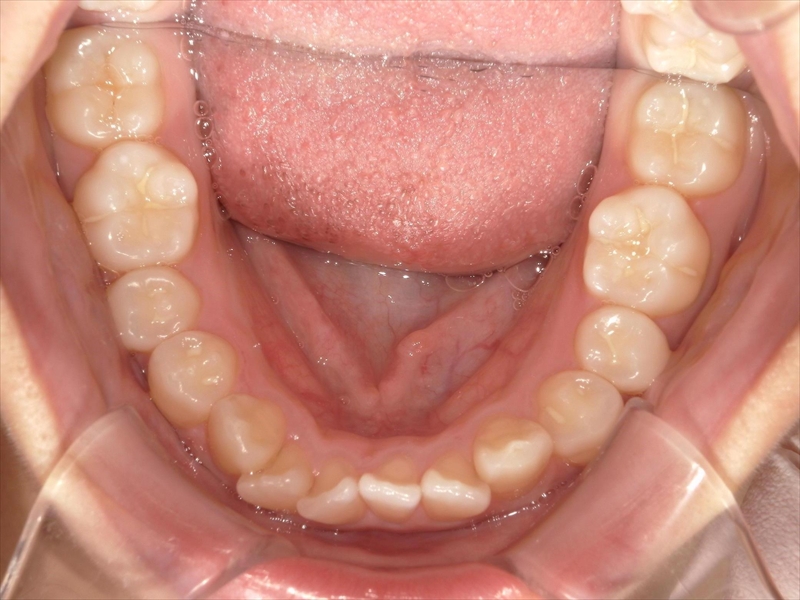

この患者様は、重度の出っ歯があり、下顎前歯には叢生が認められました。

- 上顎出っ歯が原因で下顎前歯が上に伸び過ぎているため、圧下

- 犬歯から小臼歯までが捻じれていたため、正しい位置へ

- 大臼歯は内側へ入れ

- これらのスペースを確保するため、歯を削る(IPR)

治療前後 写真